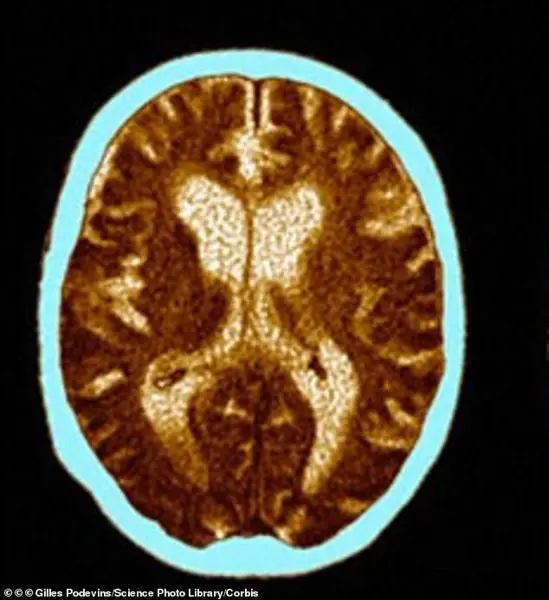

Her brain scan reveals the devastating toll of Alzheimer’s: atrophy in critical regions and dilated ventricles.

Yet, the study suggests that the signs of her condition may have been visible long before her symptoms emerged.

The wrinkles on her face, once dismissed as a natural part of aging, could have been an early warning signal.